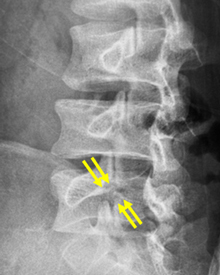

第4腰椎に前屈時に増強するすべりを認め不安定性を示しています。

MIS-TLIF(低侵襲腰椎後方椎体間固定術) 椎間板にケージと言われるスペーサーが挿入され、また経皮的に椎弓根スクリューの挿入とロッドの連結がなされ、第4腰椎のすべりが矯正され固定されています。